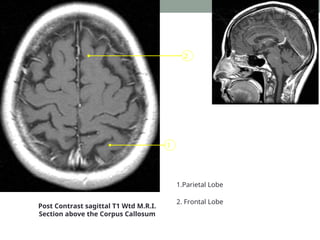

At the level of body of corpus callosum

1

2

Post Contrast sagittal T1 Wtd M.R.I.

Section above the Corpus Callosum

1.Parietal Lobe

2. Frontal Lobe